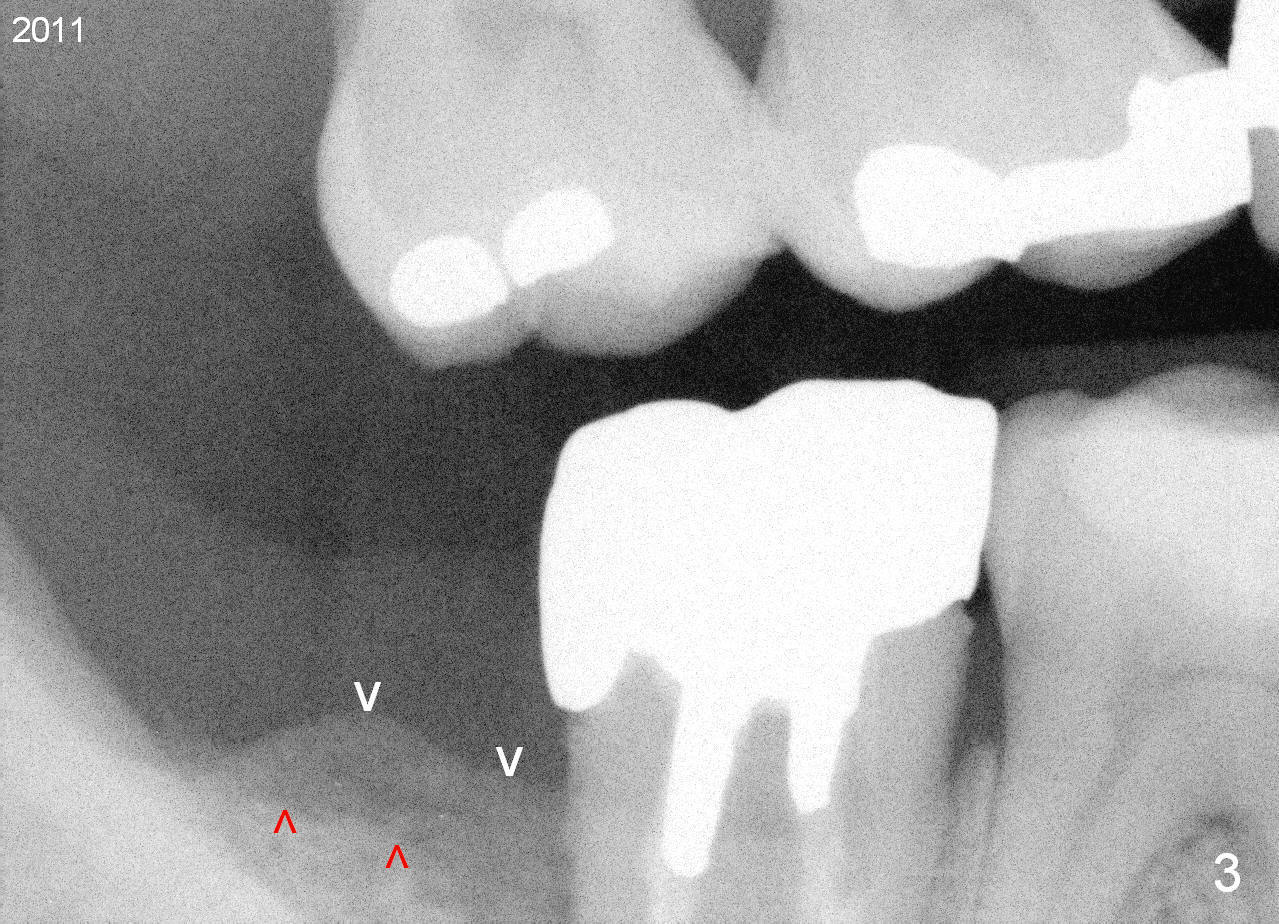

A 44-year-old man has had an asymptomatic distal defect of the tooth #31 for 8 years (Fig.1-5). Recently there is an acute episode of swelling and pain. A fistula develops mesiobucally. Panoramic X-ray films tend to show that the distal defect is deep (Fig.2,5; yellow dashed line: upper border of the Inferior Alveolar Canal). In addition, the distal defect may be not even buccolingually, as indicated by white and red arrowheads in Fig.3,4. Following placement of a 6.9x10 mm bone-level implant, a 7.8x4 (4.5) mm cemented abutment is inserted for try in (Fig.6). When it is fit, it is removed and a cover screw is temporarily placed. A piece of Osteotape (~10x4 mm) is placed distobuccally or distolingually (depending upon which wall is lower). A small amount of bone graft is packed between the most coronal portion of the implant and the Osteotape. The cover screw is then removed and the abutment is re-inserted and tightened by hand. An immediate provisional is fabricated with well-trimmed margin. Reline is done if necessary for securely holding bone graft in place. A new PA is to be taken prior to surgery to determine the extent of the lesion. Photos are taken to show the mesiobuccal fistula. Return to Lower Molar Immediate Implant Xin Wei, DDS, PhD, MS 1st edition 04/12/2015, last revision 05/25/2018